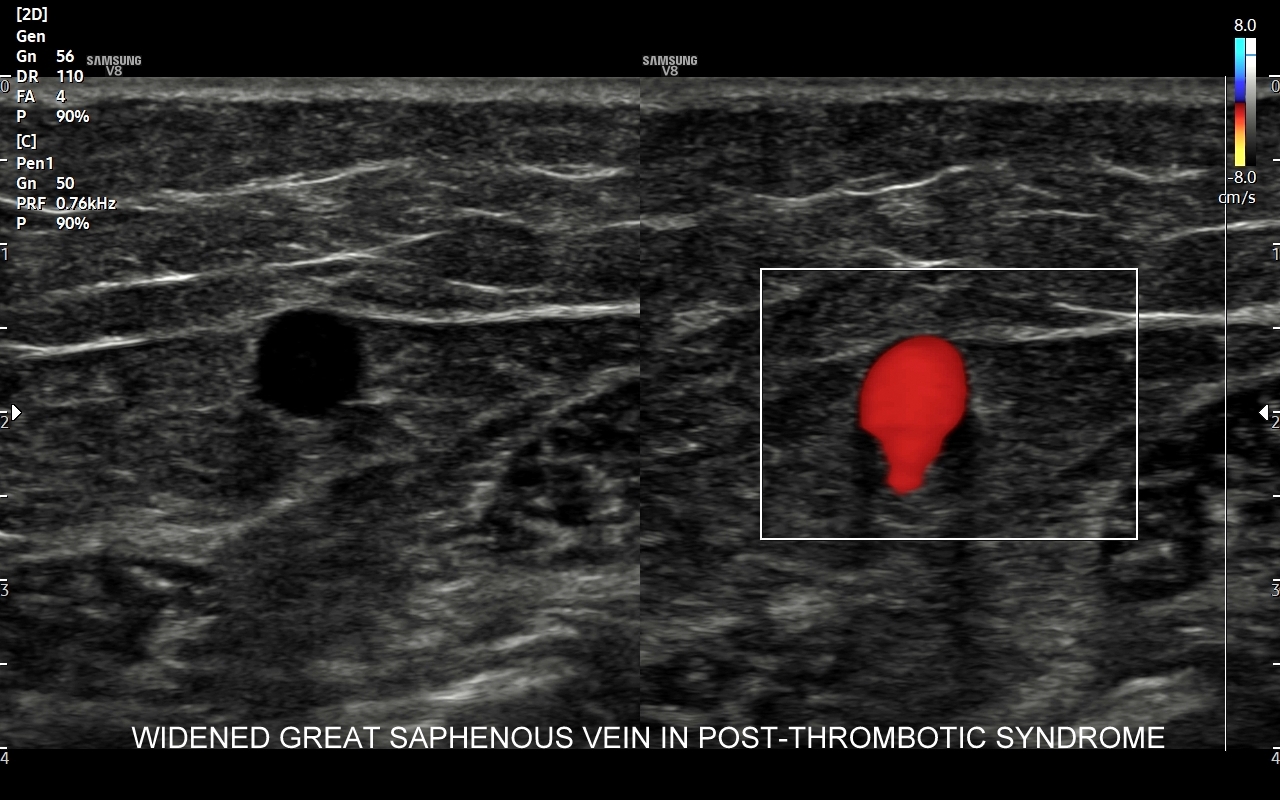

• zespół pozakrzepowy;

Czym są żylaki? Żylaki to nadmierne i niefizjologiczne poszerzenie odcinka żyły pod wpływem podwyższonego ciśnienia żylnego i zastoju krwi. W poszerzonej żyle dochodzi do zaburzenia, spowolnienia, a nawet odwrócenia kierunku przepływu krwi. Czynniki te sprzyjają wystąpieniu zakrzepicy, a także rozwoju niekorzystnych zmian w strukturze skóry i tkanki podskórnej, które zakończyć się mogą owrzodzeniem kończyny. Zdiagnozowanie przyczyny i źródła żylaków umożliwia zastosowanie celowanego zabiegu chirurgicznego

Przyczyny powstawania żylaków. Typowe żylaki powstają na skutek osłabienia i nieprawidłowego funkcjonowania zastawek żył powierzchownych (np. siedzący tryb życia, długotrwała praca w pozycji stojącej), osłabienia ścianek żył (np. podeszły wiek, długotrwałe leczenie sterydami), umiejscowionego w wyższych partiach ciała utrudnienia odpływu z układu żylnego (np. guz jamy brzusznej, niewydolność serca, ciąża, otyłość). Czynnikami ryzyka rozwoju żylaków są także obciążenie genetyczne, podeszły wiek oraz płeć żeńska. Rzadsze przyczyny żylaków obejmują nabyte niedrożności żył, zespół pozakrzepowy i malformacje naczyniowe.

USG Doppler żył kończyn dolnych

Badanie USG żył kończyn dolnych najczęściej wykonywane jest w ramach diagnostyki niewydolności żył powierzchownych oraz ich objawów w postaci pajączków żylnych, żylaków kończyn dolnych, obrzęków i owrzodzeń żylnych. Kolejnym pod względem częstości wskazaniem do badania Doppler żył jest podejrzenie zakrzepicy żył głębokich kończyn dolnych, monitorowanie leczenia zakrzepicy oraz ocena jej powikłań odległych. Powikłaniem nieleczonej zakrzepicy żył głębokich może być zespół pozakrzepowy manifestujący się masywnymi obrzękami kończyny i zaburzeniami troficznymi. Badanie USG Doppler żył kończyn dolnych często uzupełniane jest oceną układu żył centralnych w miednicy i jamie brzusznej. W tych obszarach również pojawiać się mogą żylne zmiany zakrzepowe, niedrożności żył, a nawet zmiany nowotworowe.